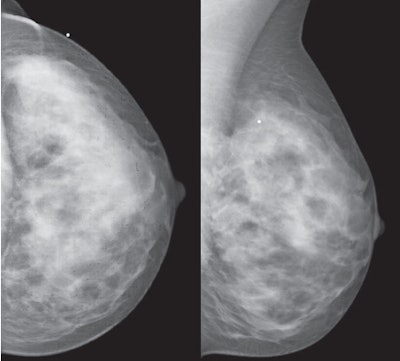

| 35-year-old woman who presented with palpable left breast lump. Whole-breast craniocaudal (above left) and mediolateral oblique (above right) and spot-magnification craniocaudal (below left) and mediolateral (below right) mammographic images show no abnormality at area of clinical concern, marked by BB. All images courtesy of the American Roentgen Ray Society. |